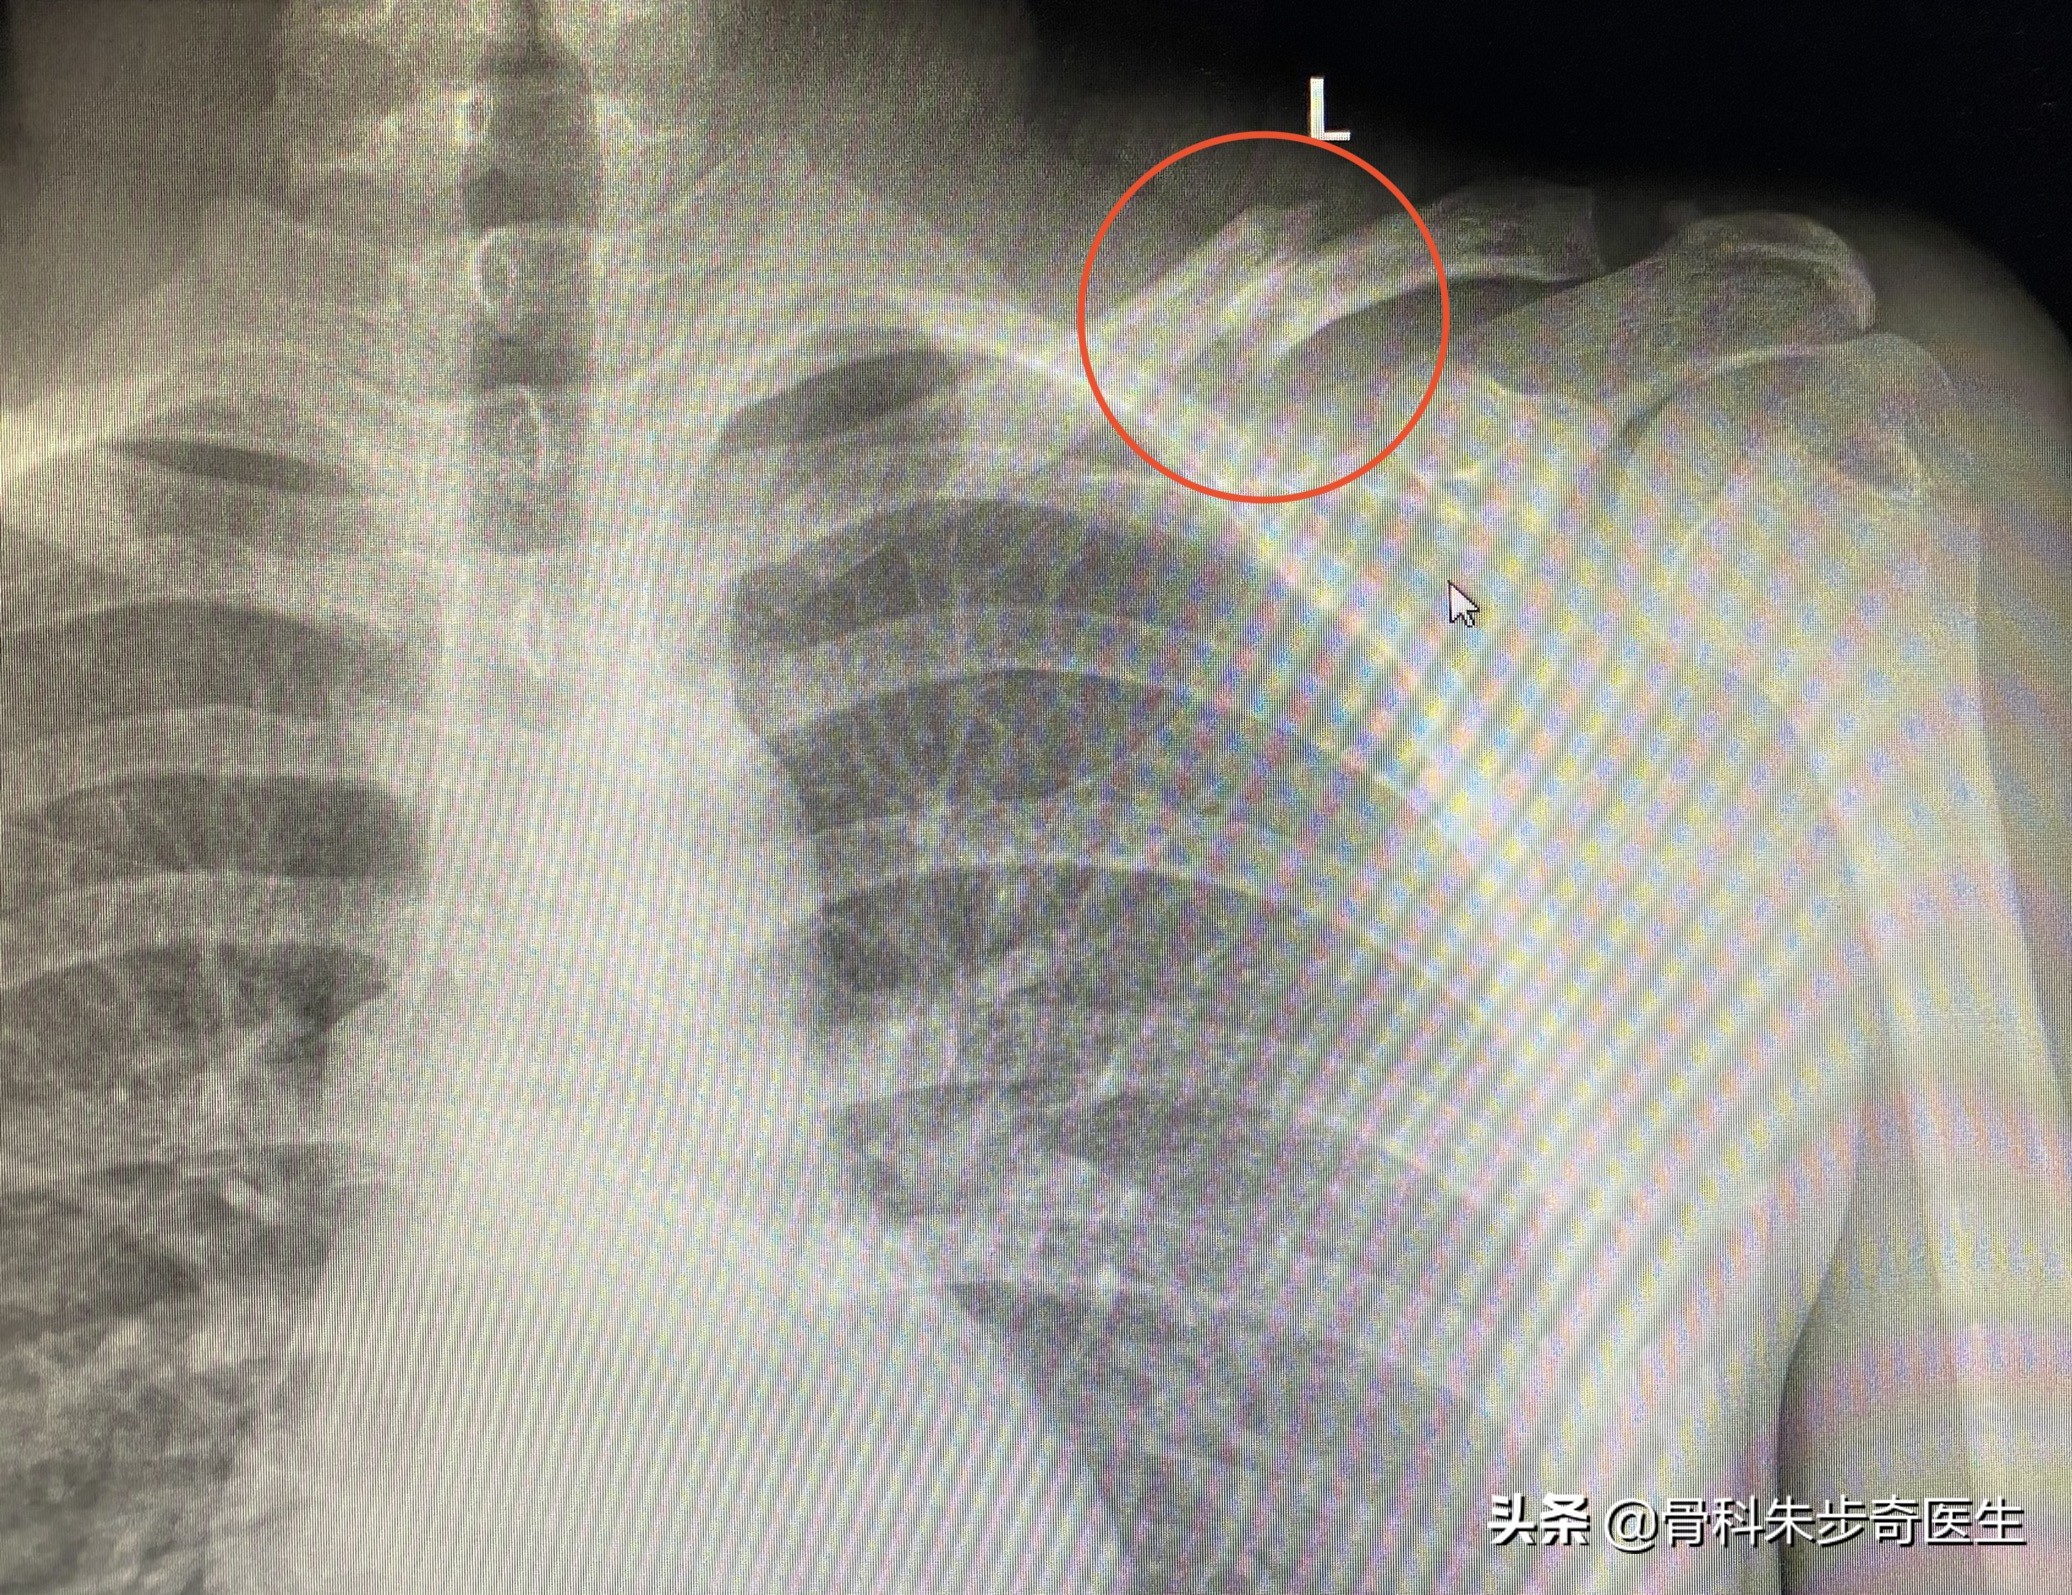

因为片子是在我们医院照的,从系统里调出来片子,看了一下,片子如下:

可以看得出来,是左侧的锁骨骨折。